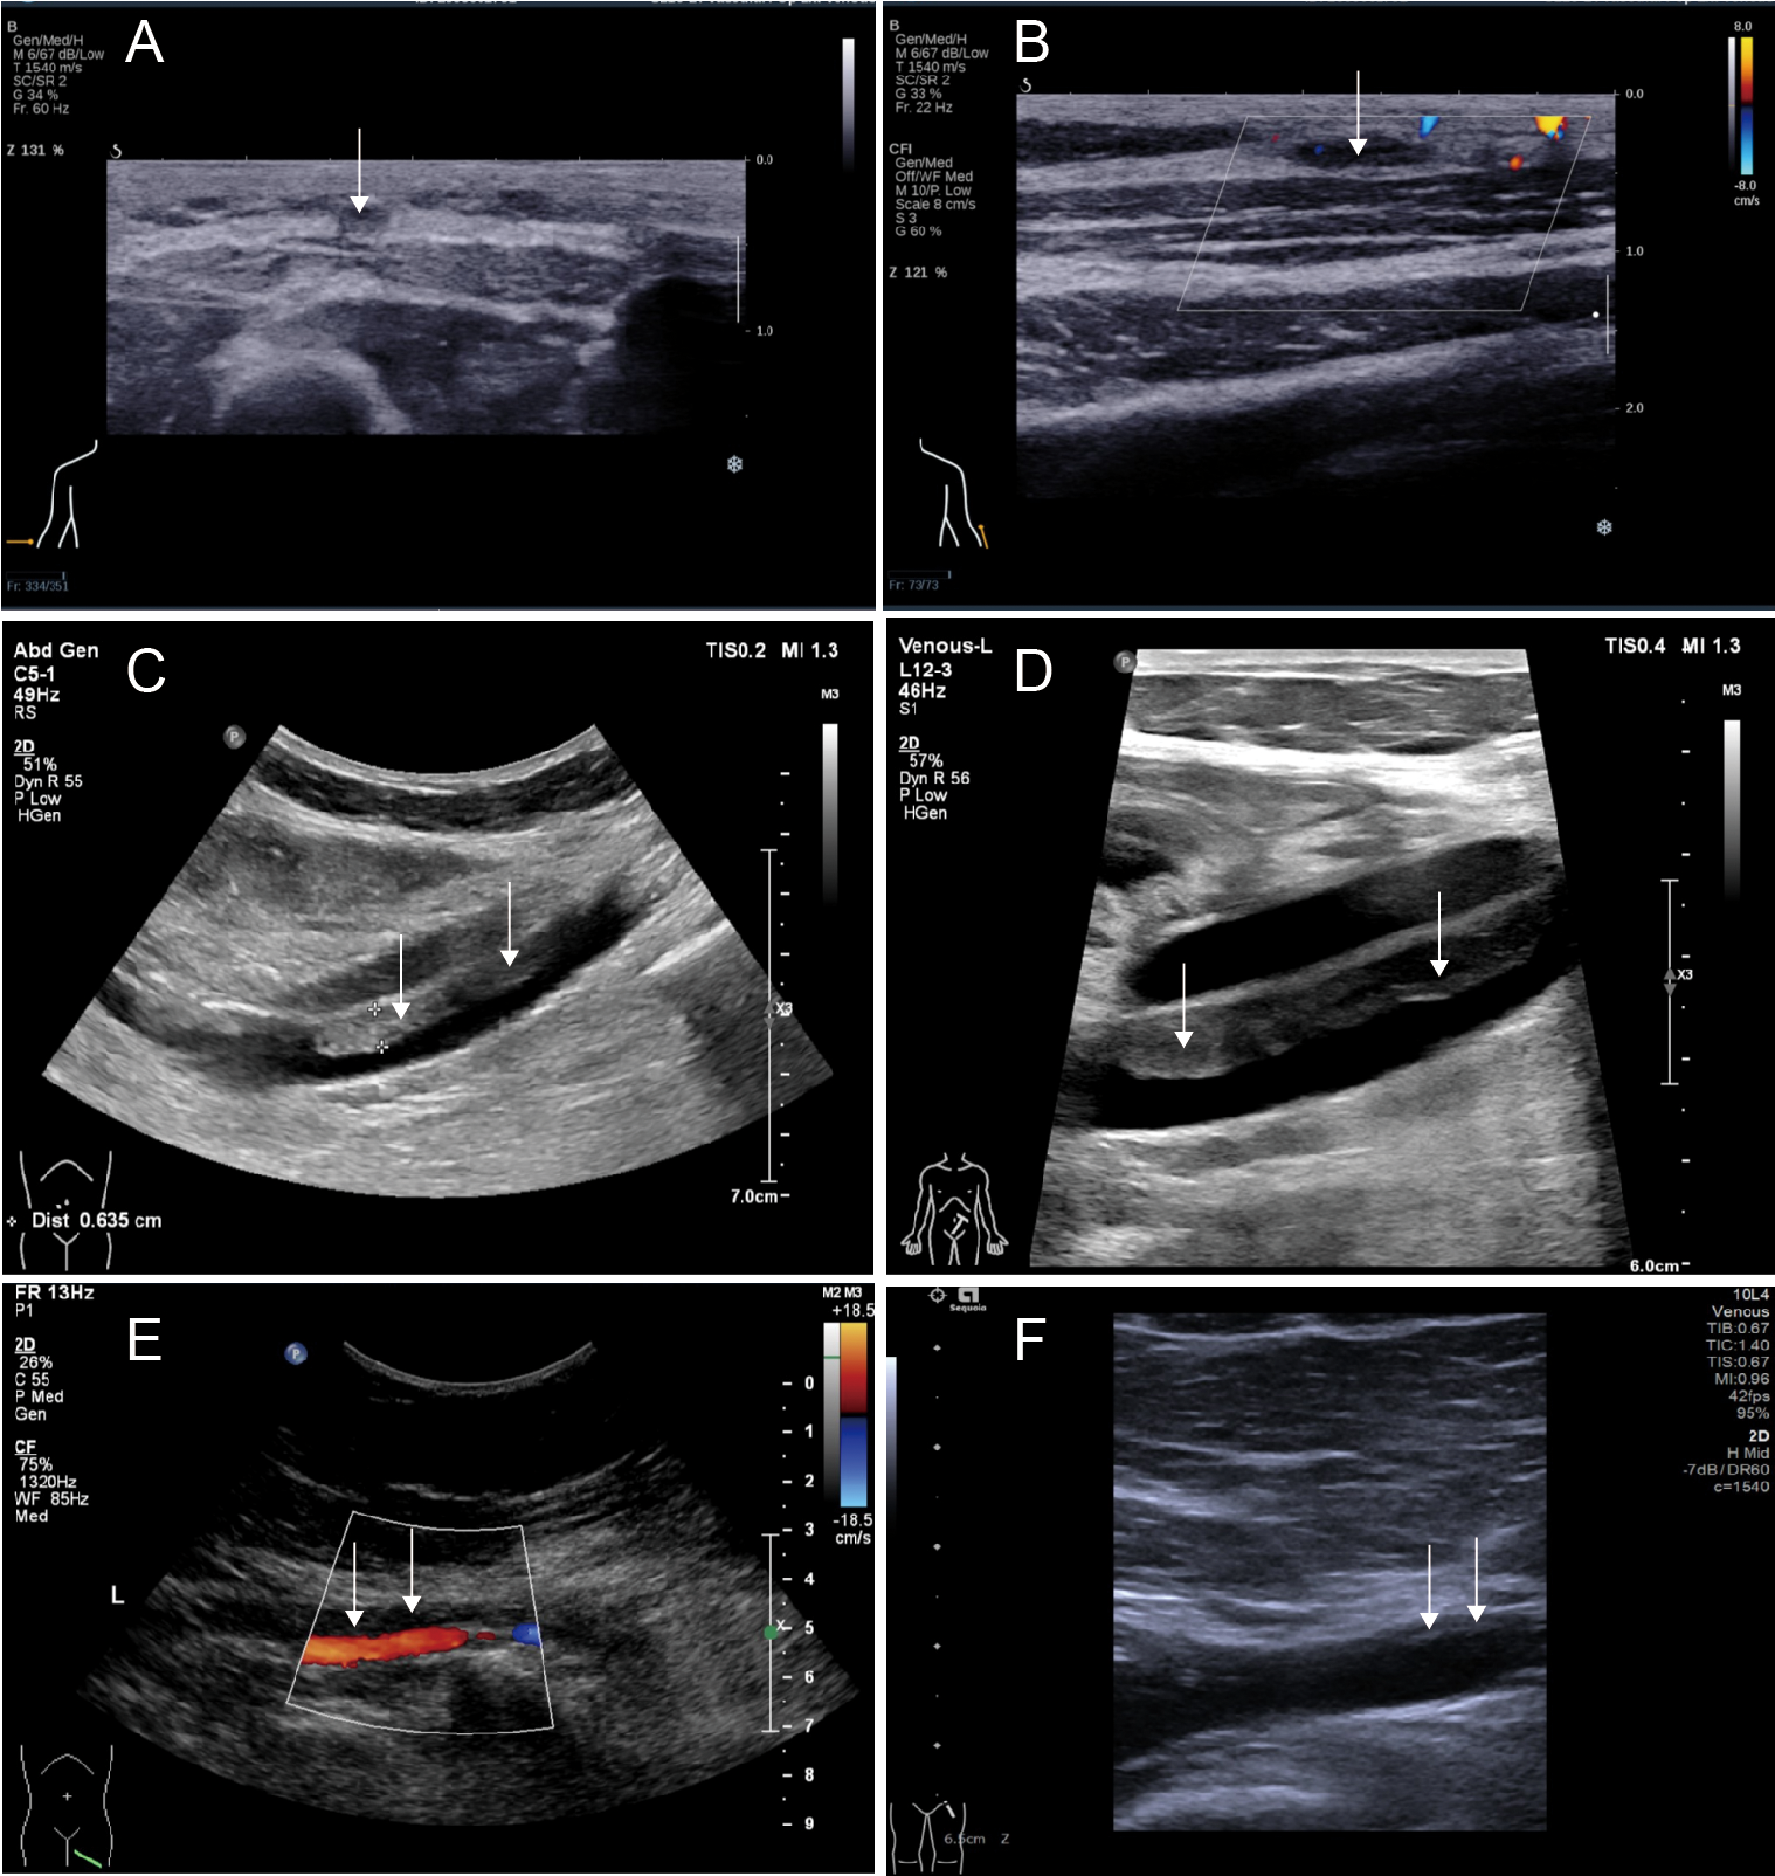

Figure 1

Phenotypic manifestations of Madelung disease. (A, B) Frontal and lateral view of bilateral thighs; (C, D) magnetic resonance imaging showing coronal and cross section of bilateral thighs; (E, F) histopathological assessment of the excised tissue revealing an adipogenic lesion.

After the liposuction surgery, the patient exhibited dark red coloration in the left thigh skin flap, along with epidermal detachment and scab formation. Concurrently, priapism and scrotal swelling were observed. Then left thigh debridement was conducted, and the patient experienced occasional exacerbation of priapism. Each instance of penile cavernous body suction and lavage provided slight relief. Penile and vascular ultrasound examinations showed no abnormalities, and the patient declined the penile head-cavernous body shunt operation. However, on the fourth day after the left thigh debridement, the patient's priapism symptoms dramatically worsened, accompanied by intolerable pain and significant hematuria. Laboratory blood tests revealed many indicator values surpassing the established reference compared with the results during hospitalization (Table 1). Alterations in indicators such as C-reactive protein and Interleukin-6, substantiated the progression of infection. Especially, the coagulation indicator tests revealed the D-dimer and fibrin and fibrinogen degradation products (FDP) levels surged to 38.00 mg/L FEU and 80.0 mg/L respectively (Figure 2). Lower abdominal computed tomography angiography (CTA) indicated right internal iliac vein embolism, while urological ultrasound demonstrated right hydronephrosis and ureteral dilatation. Subsequent bladder irrigation and anticoagulant treatment led to partial improvement in the patient's condition. The anticoagulant treatment strategy was continuously adjusted based on Caprini assessment results, blood coagulation indicators, and imaging findings. Initially, 60 mg of enoxaparin sodium was administered for four consecutive days, followed by 60 mg of nadroparin calcium for 16 consecutive days. After stabilization, 60 mg of edoxaban tosilate tablets were administered orally daily for 2 months. Additionally, wound area secretion culture suggested successive infections with Escherichia coli, Acinetobacter baumannii, and Klebsiella pneumoniae. Intravenous administration of ceftriaxone sodium, tigecycline, imipenem-cilastatin sodium, and colistin sulfate, along with the topical application of silver sulfadiazine, constituted the spectrum of antibiotics employed in practice. During anticoagulation therapy, the extremity venous ultrasound suggested the development of bilateral cephalic vein thrombosis (Figures 3A,B), along with left common femoral vein reflux and bilateral calf soft tissue swelling. Abdominal venous ultrasound revealed bilateral external iliac venous mural thrombus (Figures 3C,D). Subsequently, the patient underwent skin grafting for the traumatized area of the left thigh, with the donor areas being successively the right thigh and scalp. Follow-up extremity venous ultrasound revealed left popliteal vein thrombosis and left common femoral vein thrombosis (Figures 3E,F). When the patient was discharged from the hospital 10 days after the fourth surgery, most of the skin graft pieces exhibited good viability and the peritraumatic flap demonstrated an appropriate fit. Additionally, an improvement in priapism and swelling was observed. The patient was advised to continue oral anticoagulant therapy, with regular monitoring of coagulation function and venous ultrasound reviews.